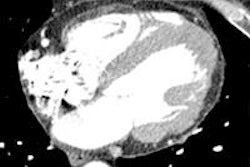

Meanwhile, high image quality was maintained in the sparse sampling technique, which will continue to evolve with further studies, according to Dr. Juerg Schwitter, director of the Cardiac MR (CMR) Center and associate professor at University Hospital Lausanne, Centre Hospitalier Univérsitaire Vaudois, and colleagues, who concluded that accurate and reproducible measurements of LV volumes and function can be obtained in a single breath-hold using the multislice CS cine MR sequences.

The CS acquisitions maintained high image quality in 94% of subjects, maintaining qualitative accuracy in LV systolic function (above) and with excellent correlation (r = 0.96, slope = 0.97, p < 0.00001). Finally, intra-/interobserver agreement for all CS parameters was good (slopes: 0.93-1.06, r: 0.90-0.99), the group reported.